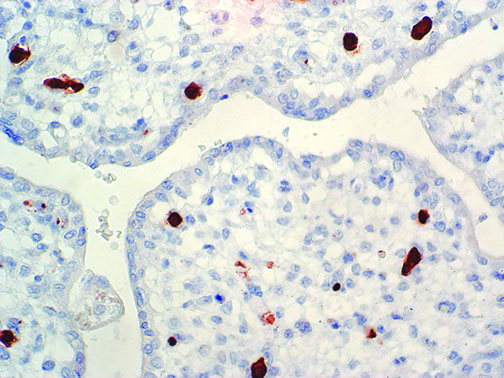

It is the ICU physician who is most likely to witness one of the deadliest manifestations of the abnormal immunological response, the cytokine storm syndrome (CSS). This response is also referred to by some as the cytokine release syndrome (CRS). CSS is characterized by continuous activation and expansion of macrophage and lymphocyte populations, which secrete large amounts of cytokines, causing the cytokine storm. This massive cytokine release is akin to hemophagocytic lymphohistiocytosis (HLH) disease, a syndrome characterized by initial unchecked and persistent activation of cytotoxic T lymphocytes and NK cells.

Clinical and laboratory manifestations of HLH include fever, enlarged liver and/or spleen, neurologic dysfunction, coagulopathy, liver dysfunction, cytopenias (i.e., low levels of erythrocytes, leukocytes, and/or platelets), hypertriglyceridemia, hyperferritinemia, hemophagocytosis, and eventually diminished NK cell activity as the immune system becomes progressively paralyzed. HLH can be familial (primary HLH) or secondary to another disease process (sHLH), such as rheumatic disease, in which it is referred to as macrophage activation syndrome (MAS, characterized by elevated ferritin).